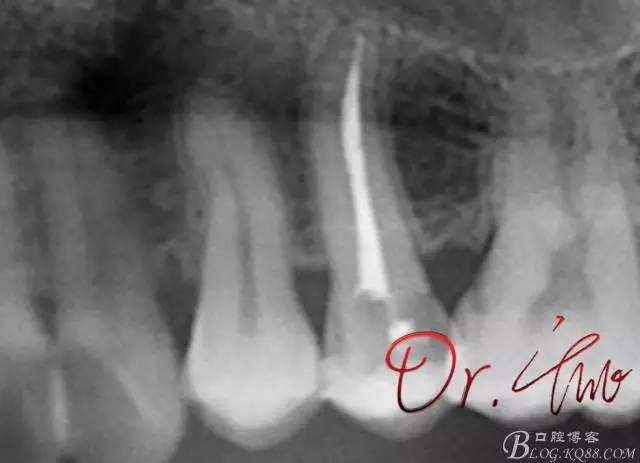

先來第一個病例

初診照

拍片確定長度